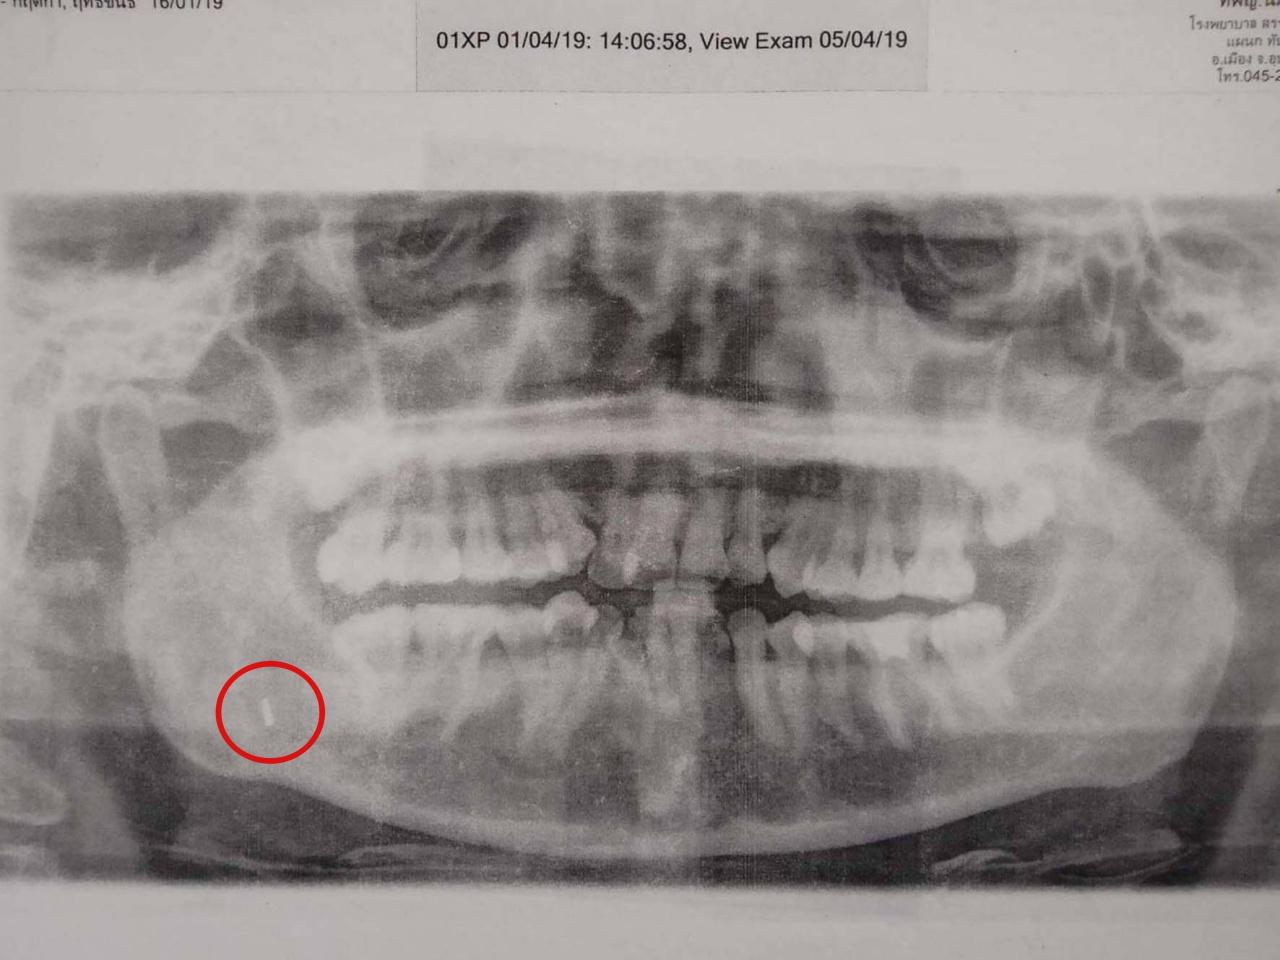

นางกฤติกา เปิดเผยว่า ย้อนไปเมื่อปี 2558 แพทย์โรงพยาบาลแห่งหนึ่งใน จ.นราธิวาส ได้ทำการผ่าตัดรักษาอาการฟันคุด แล้วลืมหัวกรอฟันไว้ในเหงือก กระทั่งเมื่อปีที่แล้วแพทย์ทันตแพทย์ศาสตร์ มข. ได้ตรวจ และทำการผ่าตัดนำหัวกรอฟันออกมาได้ แต่ก็ต้องมีการนัดติดตามอาการทุกๆ 6 เดือน